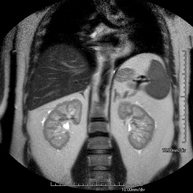

Prova diagnòstica no invasiva que consisteix en l'obtenció d'imatges d'alta definició anatòmica del fetge mitjançant l'ús d'un camp electromagnètic i ones de ràdio (amb un emissor i un receptor). No utilitza radiació ionitzant. Es realitza per estudiar qualsevol lesió localitzada en el fetge. Normalment es requereix l'ús de contrast paramagnètic (Gadolini) per caracteritzar les lesions. És necessari realitzat la prova en dejú (6 hores). - RM de Ronyons

Prova diagnòstica no invasiva que consisteix en l'obtenció d'imatges d'alta definició anatòmica d'ambdós ronyons mitjançant l'ús d'un camp electromagnètic i ones de ràdio (amb un emissor i un receptor). No utilitza radiació ionitzant. Es realitza per estudiar qualsevol lesió localitzada en ambdós ronyons. Normalment es requereix l'ús de contrast paramagnètic (Gadolini) per caracteritzar les lesions. - RM Glándulas Suprarrenales